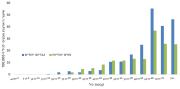

| 04:39, 14 באוגוסט 2023 | היארעות סוכרת 1.png (קובץ) |  |

285 קילו־בייטים | Motyk | 1 | |